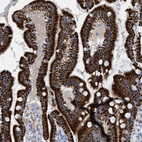

Immunohistochemical staining of human cerebellum shows strong granular cytoplasmic positivity in Purkinje cells.